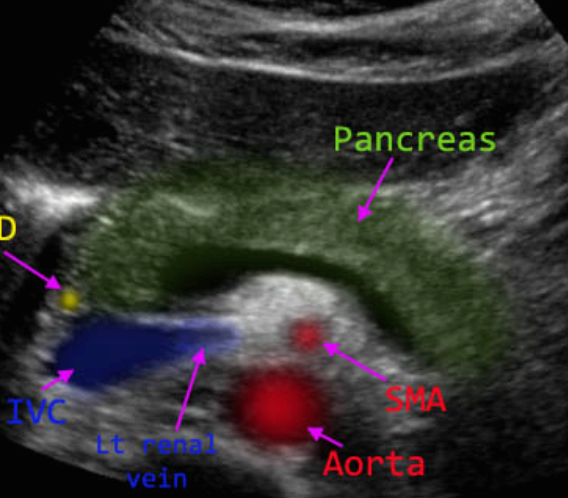

췌장과 주변 혈관들과의 관계 (pancreatic vascular and ductal landmarks)

췌장은 후복막강 장기로 주변 장기에 의해 영향을 많이 받아 초음파적으로 찾기 힘들기 때문에 주변혈관을 landmark로 찾아야 한다.

① 하대정맥 (IVC)

인체의 정중선에서 우측에 있고 췌장 두부의 바로 뒤쪽에 위치한다. 췌두부의 종괴는 하대정맥을 압박하거나 폐색 할 수도 있다.

② 대동맥(Aorta)

인체의 정중선의 좌측에 있고 췌체부와 상장간막동맥 뒤에 위치한다.

③ 상장간막정맥(SMV)

비장정맥과 이어져 있고 구상돌기(uncinate process) 앞에 있다.

④ 상장간막동맥(SMA)

췌장 체부의 뒤쪽과 대동맥의 앞쪽에 위치한다.

⑤ 비동맥(Splenic artery)

췌체부의 위쪽 췌미부의 뒤쪽에 위치하고 비문(splenic hilum)으로 들어간다.

⑥ 비정맥(Splenic vein)

췌장 뒤에 위치하여 상장간막정맥(SMV)과 만나 간문맥(portal vein)을 형성한다.

⑦위십이지장동맥(Gastroduodenal artery)

췌두부의 앞쪽으로 지나간다

⑧원위 담관(Distal CBD)

하대정맥 앞쪽에 있고 췌두부의 뒤쪽을 관통하여 십이지장으로 들어간다.